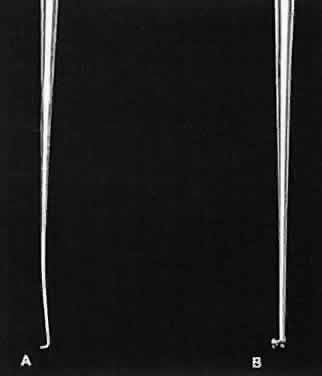

Fig. 14. When a proper degree of force is applied to the instrument, the tips will align properly. However, if greater forces are applied, the instrument bends and the jaws do not appose correctly.